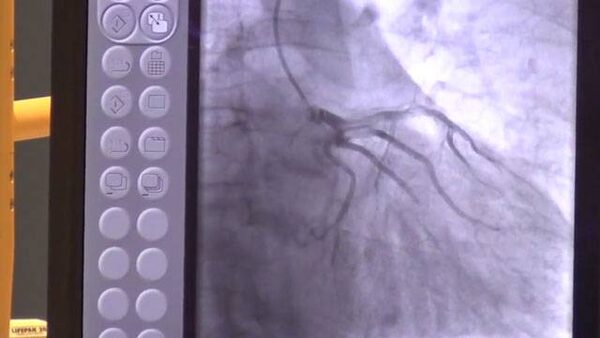

Angiogram

The study, published in the Annals of Internal Medicine on March 9, looked at 48,336 patients with stable ischemic heart disease, or angina, who received an angiogram, a test that takes x-ray pictures of the coronary arteries, a test that takes x-ray pictures of the coronary arteries and the vessels that supply blood to the heart.